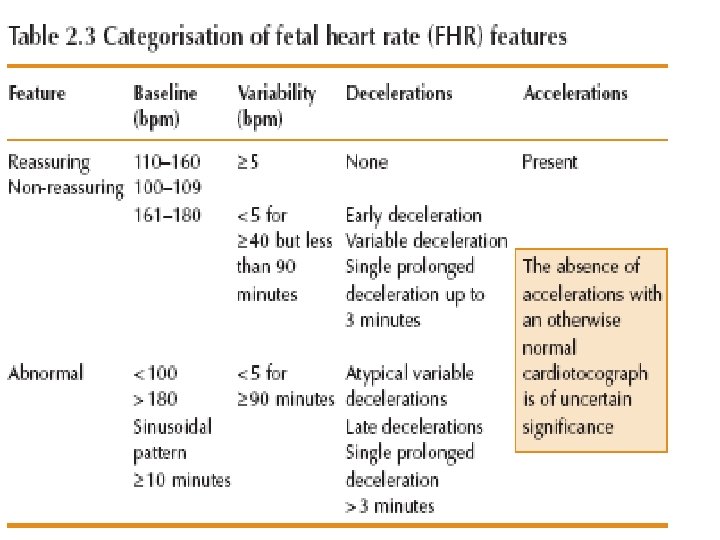

Baseline variability The minor fluctuations in baseline FHR occuring at three to five cycles per minute. It is measured by estimating the difference in beats per minute between the highest peak and lowest trough of fluctuation in a one-minute segment of the trace.

FHR Variability Absent variability = Amplitude range undetectable Minimal = < 5 BPM Moderate = 6 to 25 BPM Marked = > 25 BPM

Causes of Decreased Variability • • Fetal metabolic acidosis CNS depressants Fetal sleep cycles Congenital anomalies Prematurity Fetal tachycardia betamethasone

Early Deceleration Gradual decrease in FHR with onset of deceleration to nadir >30 seconds. The nadir occurs with the peak of a contraction.

Late Deceleration Gradual decrease in FHR with onset of deceleration to nadir >30 seconds. The nadir of the deceleration occurs after the peak of the contraction

Variable Deceleration Abrupt decrease in FHR of > 15 beats per minute measured from the most recently determined baseline rate. The onset of deceleration to nadir is less than 30 seconds. The deceleration lasts > 15 seconds and less than 2 minutes. A shoulder, if present, is not included as part of the deceleration. Variable decelerations may be observed in up to 50% of NSTs. If nonrecurrent and <30 seconds, they are of no clinical significance.

Variable Deceleration Typical: • shoulders Atypical : • Overshoot • Loss of primary shoulder • Slow return to baseline (late component) • Baseline returns to a lower level(after deceleration) • Biphasic(W shape) • loss of variability during deceleration

Classification severity of variable deceleration • Mild: duration < 30 second or depth up to 80 bpm • Moderate : deceleration < 80 bpm • Severe : deceleration < 70 bpm for more than 60 second